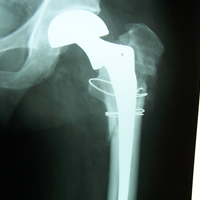

Case:7 Fracture Neck Femur with Implant failure and Re-Fixation with hemi-arthroplasty

Alcoholic Gardener by profession had slipped in bathroom & fell. He sustained fracture neck femur.He was operated with closed reduction & CC Screw fixation under IITV. Two weeks’ post fixation he again fell & sustained fracture in sub trochanteric region. He was treated with Hem-Arthroplasty with Tension band wiring.

Post-Op

Post Prosthesis Fall

Post Uninon-3Months